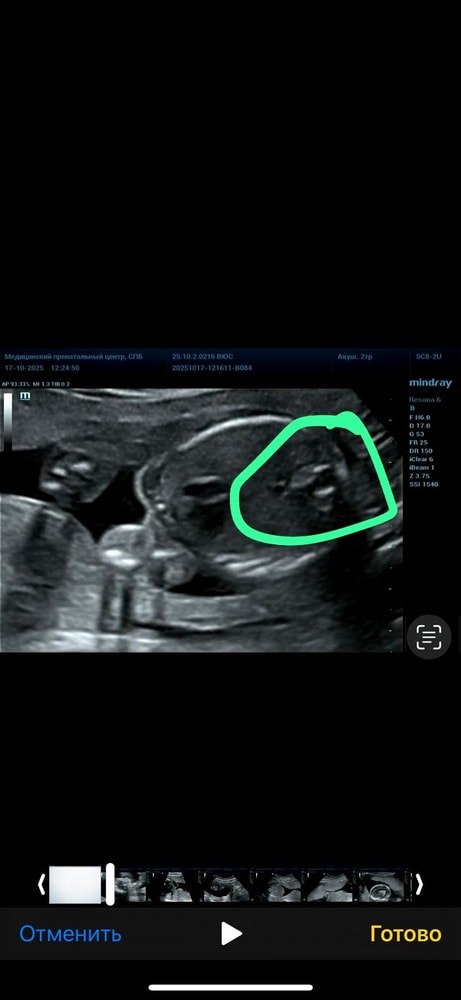

хочу выслать фото с узи, конечно понимаю что не все поймут узи, но вдруг у кого-то было похожее.